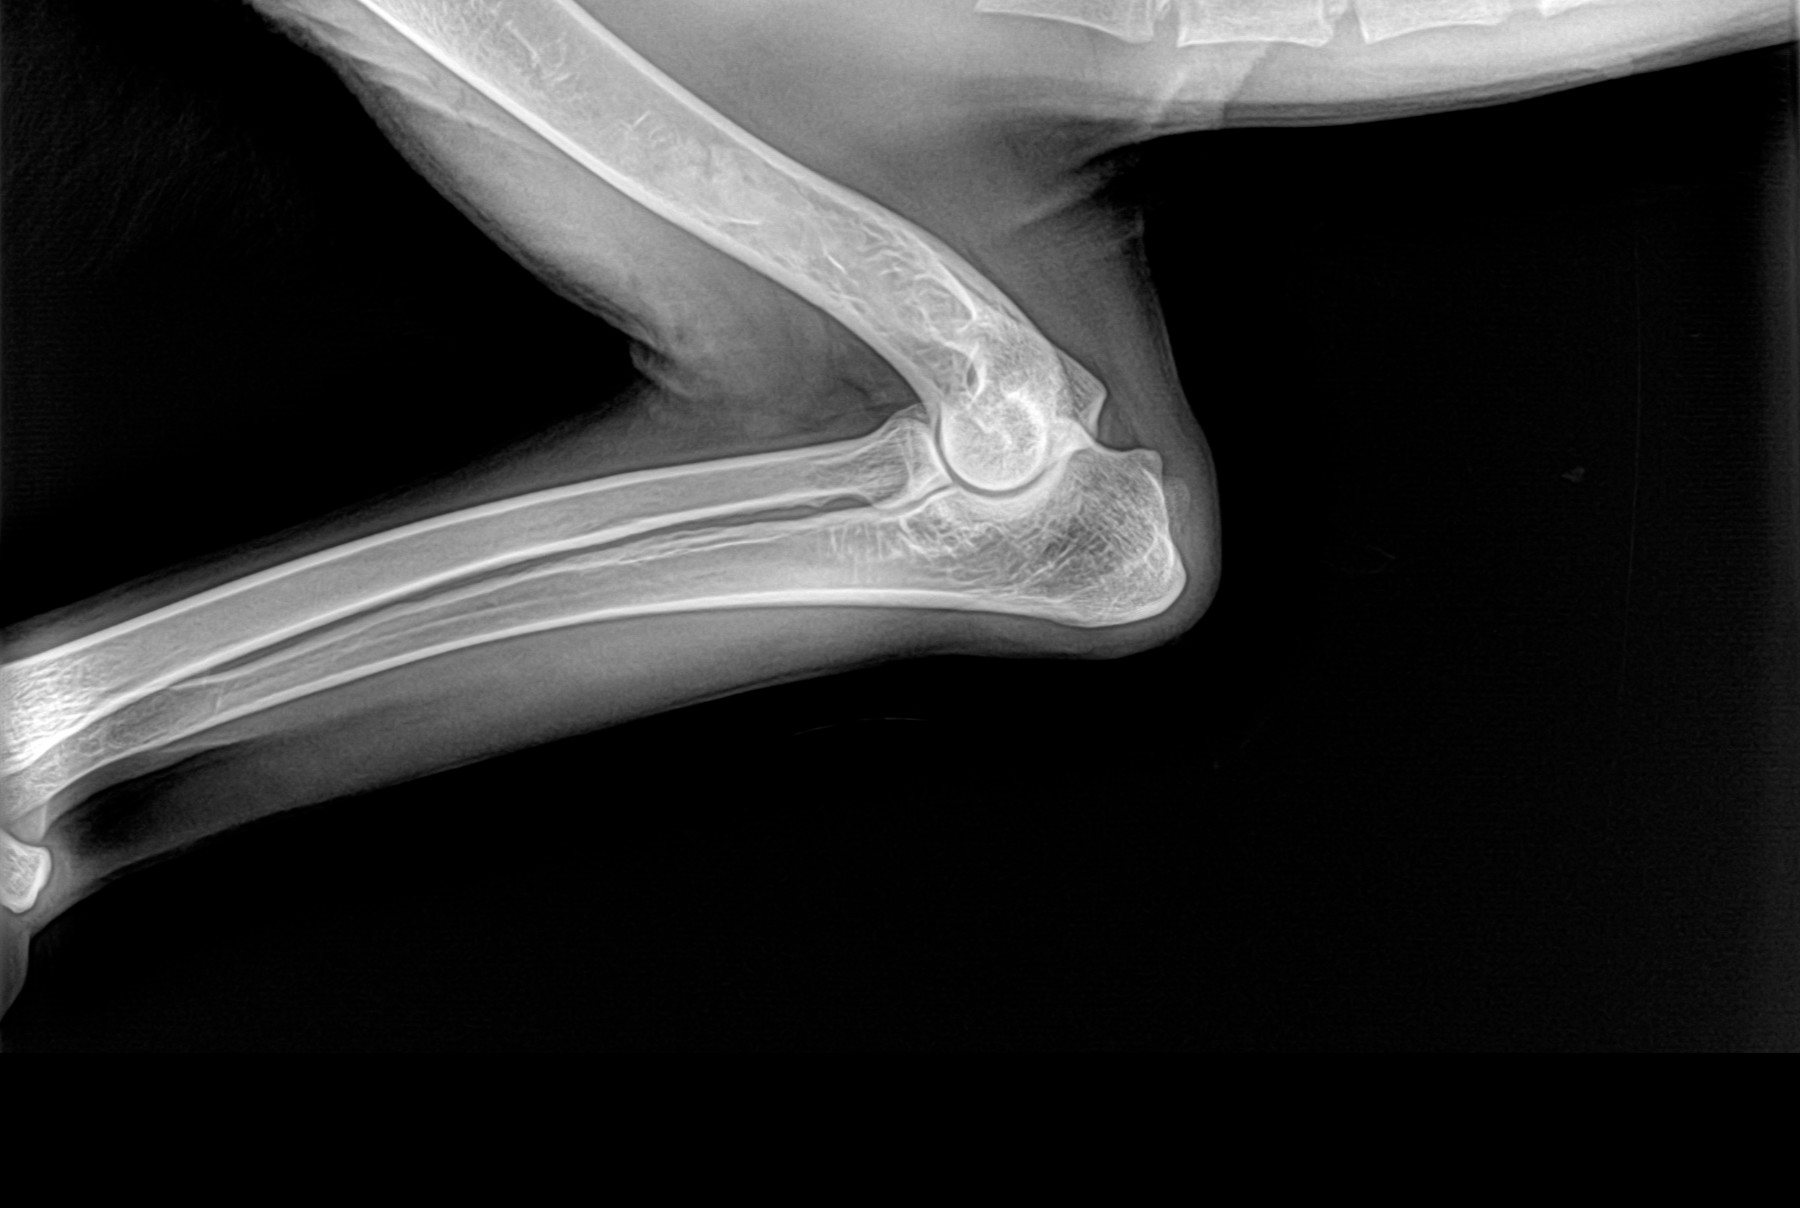

Radiología Digital como Herramienta Complementaria en el Dictamen de Bienes Muebles

Desde el descubrimiento de los rayos “X” y las placas radiográficas por Wilhelm Conrad Roentgen y su posterior difusión a través de la Asociación Físico médica de Wurzburg el 28 de diciembre de 1895, que fue la primera asociación que habló de los nuevos rayos que podían penetrar el cuerpo y fotografiar los huesos, ha habido muchos cambios tanto en la forma de obtener, procesar e incluso en la forma de visualizar, manejar y almacenar las placas radiográficas.